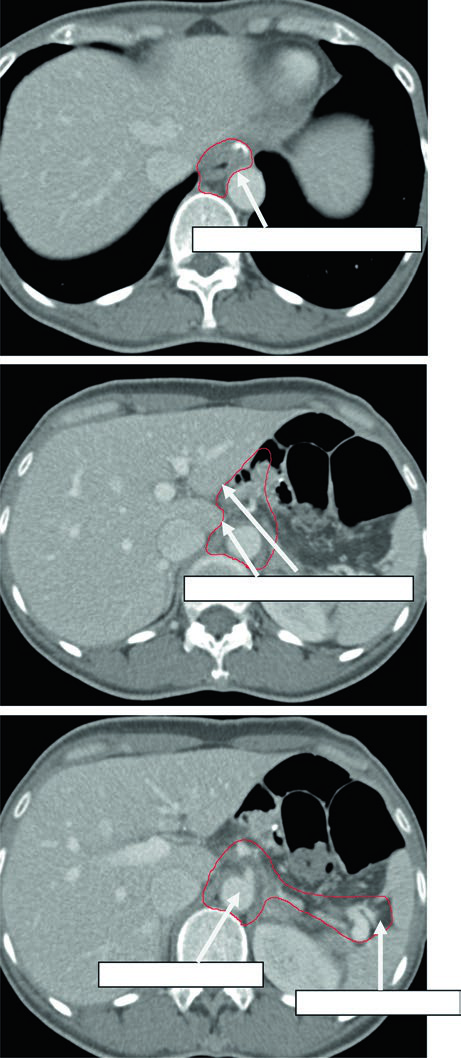

Caso 2: T3N3M0 Adenocarcinoma do Corpo — Gastrectomia Distal

Com doença T3N3, o CTV é extenso: inclui anastomose gastrojejunal, estômago remanescente, artéria celíaca, hilo esplênico e leito tumoral pancreático. Esse cenário exige atenção especial às restrições de dose nos órgãos de risco — particularmente rins e fígado — pois o volume de tratamento é considerável.